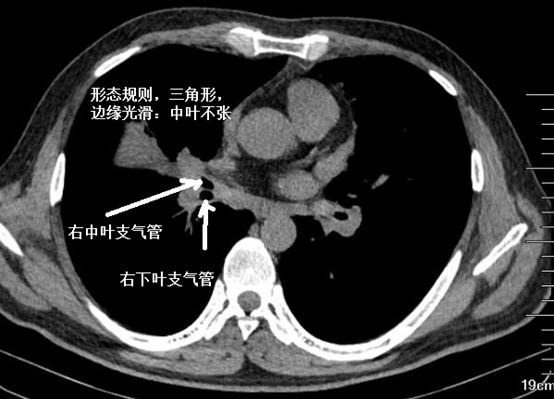

肺不张的诊断和鉴别诊断.ppt

供临床医学大专医学影像诊断用 2,肺不张 ——支气管完全阻塞时,气体

肺不张ct读片太难看完这篇文章轻松入门